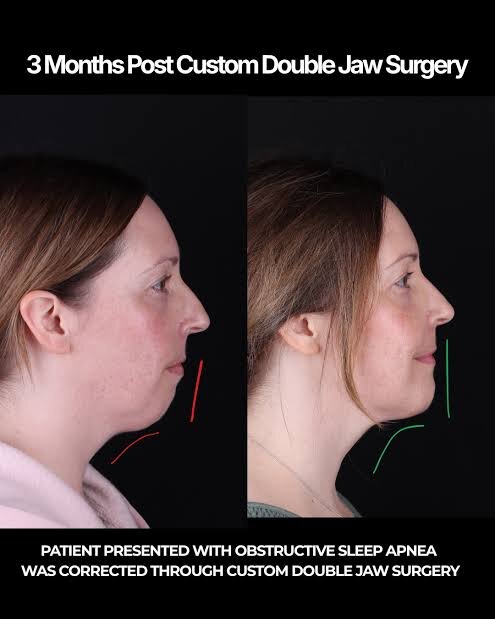

When u have a bad nose but also want to do a surgery that includes Le Fort osteotomy, u should first do Le fort since moving the maxilla can have an effect on the nose right?